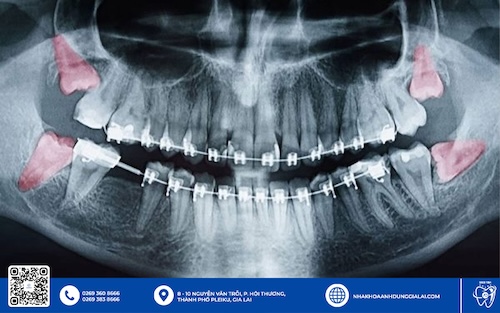

Như trường hợp khách hàng Lại Phước Khánh (31 tuổi) đến với Nha Khoa Anh Dũng trong tình trạng răng 48 mọc lệch 90 độ, bị nhồi nhét thức ăn giữa kẽ răng 47-48, gây đau nhức và có nguy cơ sâu răng số 47.